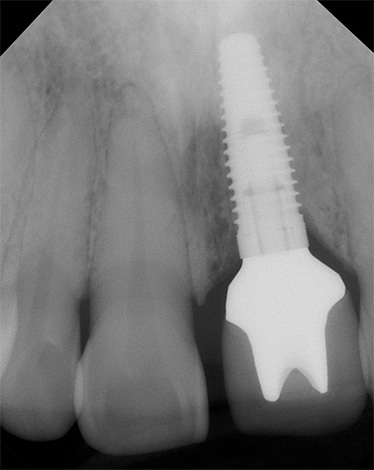

A foto abaixo mostra um exemplo de inflamação do tecido na área de um implante instalado: